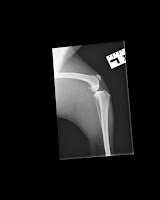

Keskiviikkona tietenkin oli yksi vuoden kiireisimmistä työpäivistä ja lääkäriin ehdin vasta alkuiltapäivästä. Domi ei edelleenkään eläinlääkäriin mentäessä käyttänyt jalkaa yhtään. Saimme onnneksi nopeasti poissuljettua akillesjänteen luksaation sekä polvilumpioluksaation. Loistavasti olivat paikallaan. Eläinlääkäri paikansi kipupisteen polveen, josta pelkona oli siis polven ristisiteen tai sivuristisiteen repeäminen. Mitään selvää polven ristisidevammaan viittavaa ei kuitenkaan tuntunut vetolaatikkotestillä. Eläinlääkäri alkoi kovasti kallistumaan pahemman revähtymän puoleen ja olisi suosittanut viikon tulehduskipulääkekuuria sekä lepoa. Minut tuntien hän kuitenkin kysyi heti haluanko, että polvi kuvataan, jolla voidaan varmuudella poissulkea asiota. Lääkkeet koiraan ja koira nukkumaan. Röntgenkuvista pystyy näkemään hyvin lievää reaktiota polven sivusiteiden alueella, mutta se ei toki mitenkään selitä voimakasta ontumista. Kuvassa polvi ei näytä olevan täysin kohdillaan, joka johtui lonkan ulkokierteestä, mutta muuten polvi näyttää oikein priimalta ja siistiltä. Ortopedi kuitenkin lausuu kuvat vielä ensi viikon alkupuolella.